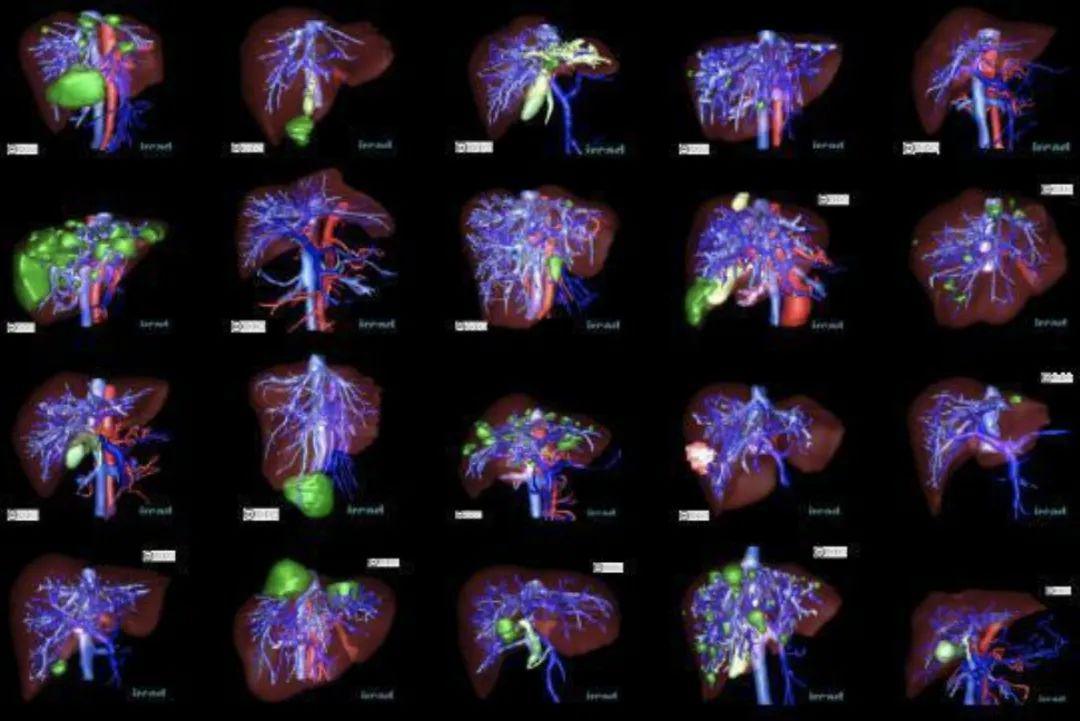

3D-IRCADB 脏器分割数据集

数据集链接:http://m6z.cn/6x5OSn

3D-IRCADb-01 数据库由 10 名女性和 10 名男性 75% 的肝肿瘤患者的 3D CT 扫描组成。20个文件夹对应20个不同的患者,可以单独下载也可以联合下载。下表提供了图像信息,例如肝脏大小(宽度、深度、高度)或根据 Couninaud 分割的肿瘤位置。它还表明肝脏分割软件可能遇到的主要困难是由于与邻近器官的接触、肝脏的非典型形状或密度,甚至图像中的伪影。